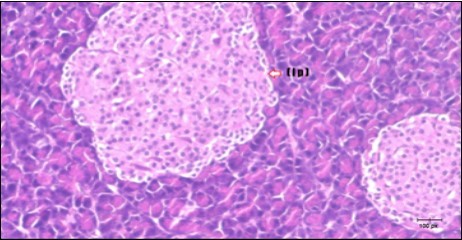

Histological examination of pancreas of the control rats showed normal sized islets of pancreas (Ip) compared to the diabetic rats which showed markedly atrophic islets of pancreas (I.p.) (Figure 8 and Figure 9). Pancreas of in groups (3) and (4) rats showed mild atrophic islets of pancreas (I.p.) with inflammatory cellular infiltrate (Figure 10 and Figure 11). The pancreas of rats in group (5) showed nearly normal islets of pancreas (I.p.) with few inflammatory cellular infiltrate (I.c.) (Figure 12).

Figure 9.Photomicrogragh of pancreas section of diabetic rat showing the markedly atrophic islets of Langerhans. (arrow) (H&E) (40X).

Photomicrogragh of pancreas section of diabetic rat showing the                  markedly atrophic islets of Langerhans. (arrow) (H&E) (40X).